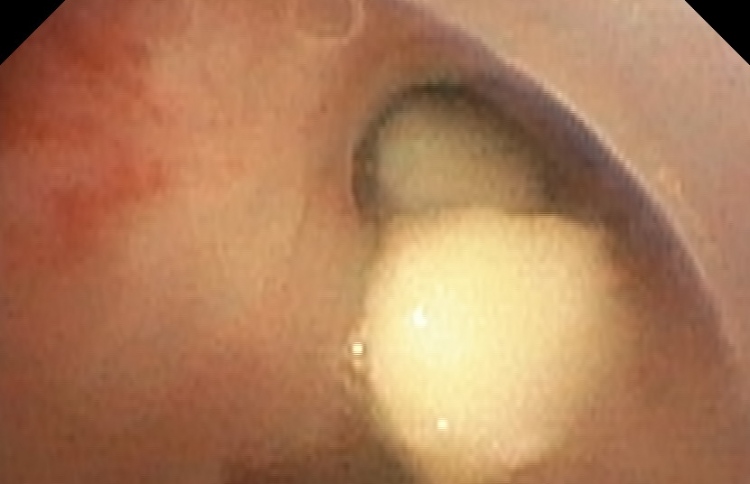

ކުޑަކުއްޖާގެ މޭގަ ތާށިވި އެތިކޮޅު އިންޑިއާއިން ނަގައިފި

ނޭވާހޮޅީގައި ކެޝޫނަޓެއް ތާށިވެ، ނުރައްކާވެއްޖެ

11 އަހަރުގެ ކުއްޖެއްގެ ފުއްޕާމެއިން ޕިނެއް ނަގައިފި